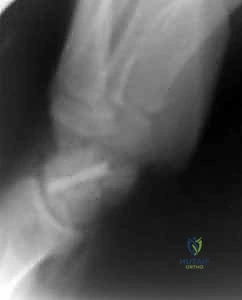

Operative Techniques in Orthopaedic Surgery